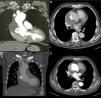

During complementary investigation, a chest X-ray showed widening of the mediastinal silhouette and a transthoracic echocardiogram revealed a pseudoaneurysm of the ascending aorta, 35 mm above the aortic valve (Figure 1A).

Imaging of ascending aortic pseudoaneurysm. (A) Transthoracic echocardiography showing ascending aortic pseudoaneurysm in parasternal view; (B) three-dimensional computed tomography (CT) reconstruction of aorta; (C) CT scan with intravenous contrast showing the dimensions of the neck and cavity of the pseudoaneurysm; (D) aortography with contrast opacification of pseudoaneurysm cavity (solid arrows).

Coronary computed tomography angiography (CCTA) (Figure 1B and 1C) and aortography (Figure 1D) confirmed a large pseudoaneurysm (98 mm×48 mm) and a defect in the aortic wall (19 mm×19 mm).

CCTA at one month (Figure 3A and B) and 12 months (Figure 3C and D) after the procedure showed the device correctly positioned and complete closure of the pseudoaneurysm with thrombosis of its cavity.

Evolution over time of ascending aortic pseudoaneurysm closure. (A and B) Computed tomography (CT) scan at one month showing Amplatzer ASD device in a stable position and organizing thrombus inside the pseudoaneurysm cavity; (C and D) CT scan at one year with device maintaining its position and partial resolution of the excluded pseudoaneurysm cavity.